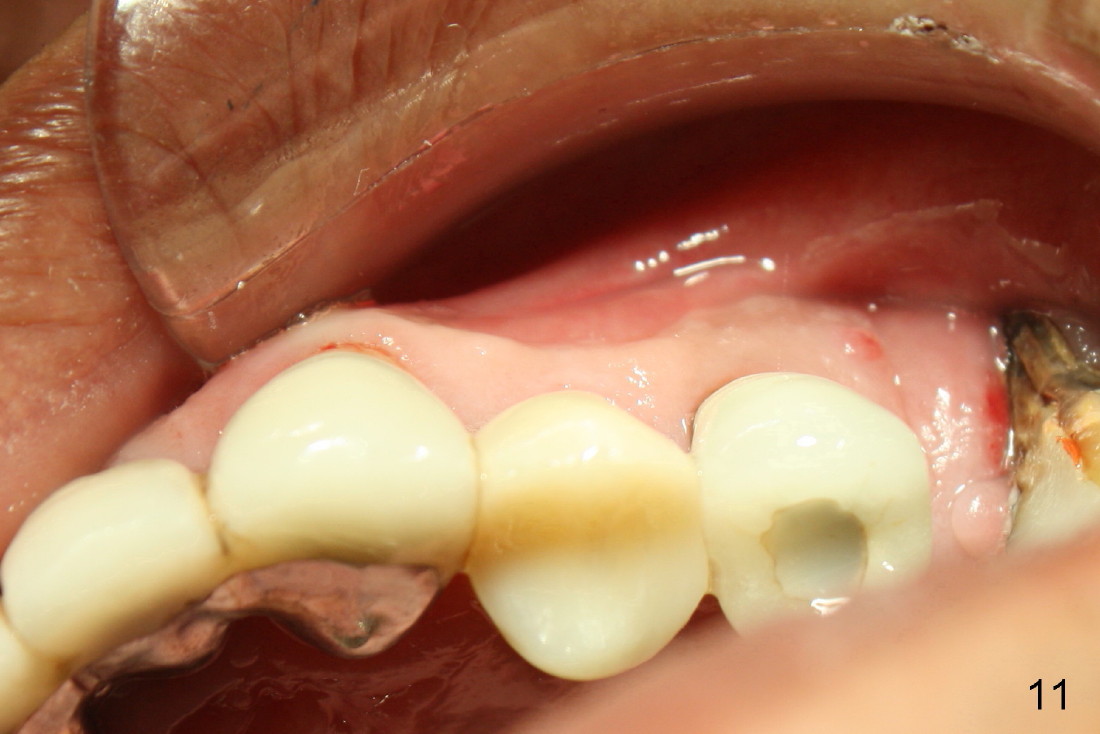

A 50-year-old man has mild pain in the upper left 1st bicuspid 3 years after root canal retreatment with placement of two posts (Fig.1). Findings of clinical exam are consistent with root fracture (Fig.2). Extraction reveals two fused roots (Fig.3,4). Probing indicates that the buccal plate is defective. Osteotomy is initiated in the palatal socket with a 2 mm pilot drill, followed by 2.5 and 3.0 mm reamers and 4.5x20 mm tap. The septum appears to have been pushed buccally (Fig.5 *) and form a new buccal wall (partially, strengthened by bone graft mentioned below) for the implant to be placed. The implant (4.5x20 mm) is placed in the palatal socket (Fig.6 *) with insertion of an abutment (A: 3.5x5 mm 0º), while a mixture of autogenous bone (harvested from reamers) and Synthograft (Bicon) is placed in the shrunken buccal socket (Fig.7; using allograft may decrease postop bony shrinkage). The bone graft is then contained by an immediate provisonal without collagen membrane or flaps. The patient is doing well postop. The gingiva is healthy (Fig.8*) when the provisional is removed 3 months postop with normal papillae (Fig.9 arrowheads). It remains the same 1 month post cementation (Fig.10,11). For further follow up, see immediate implant of the tooth #13.